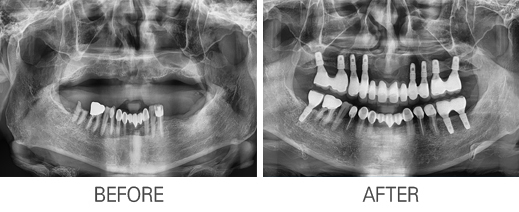

Ä«Å×°í¸®

: Àüü ÀÓÇöõÆ®

Àüü ÀÓÇöõÆ®